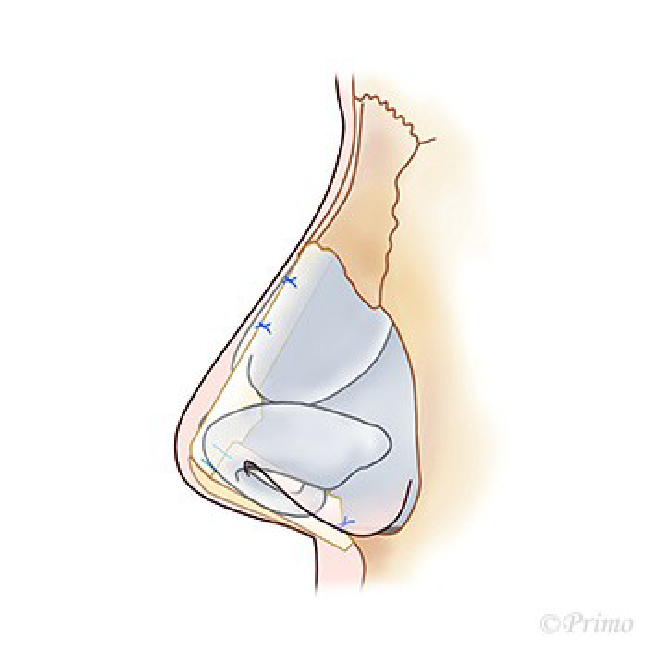

求める変化の大きさ、もともとの鼻の状態に応じ、採取部位を耳介軟骨、肋軟骨、あるいは鼻中隔軟骨から選択し、必要量のみ採取いたします。(上の図は耳介軟骨を採取して鼻中隔延長をするイメージ)

耳介軟骨からとる場合は、耳の後ろのしわに沿って約2cm程の傷から採取します。傷はほとんどわからなくなり、耳の変形も、機能障害もきたしません。

鼻中隔軟骨から採取する場合は、軟骨が小さいため、それほど大きな変化を望まない場合などになります。別の所に採取部の傷を残さない良い方法です。(下の図は鼻中隔)

アプローチは経鼻柱切開(オープンアプローチ)から、術野を広く展開し、確実に操作を行います。鼻中隔軟骨に移植軟骨を組み合わせ延長し鼻の向き、高さを変えていきます。ご希望に応じ鼻の脂肪を部分的に除去し細っそりとさせたり、インプラントによる隆鼻術を併用し、より印象的な鼻に変化させます。鼻柱の傷あとはあまり目立ちません。

青い部分が移植した軟骨です。この軟骨の固定により、鼻の高さ、細さ、向きが大きく調節できます。